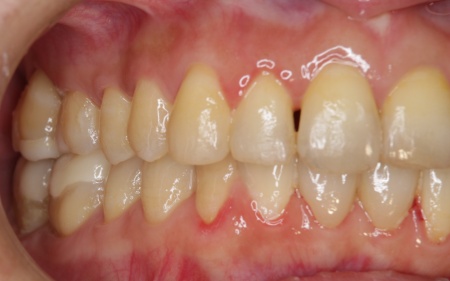

拝見したところ、歯が全体的にずれたりねじれたりして生えており、歯並びがデコボコしていました。 また、数本の歯にはプラスチックの詰め物が装着されていましたが、経年的な劣化により歯との間に段差が生じています。これも噛み合わせのバランスを崩す原因のひとつになっていると考えられました。 歯並びや噛み合わせの乱れをこのまま放置すると、歯磨きがしにくくなり虫歯や歯周病のリスクが高まるほか、特定の歯に強い力がかかり続けることで将来的に歯の寿命に影響を及ぼすおそれもあります。

以上のことから、見た目だけでなくお口全体の噛み合わせまで考慮した治療が必要と診断しました。 |

治療前